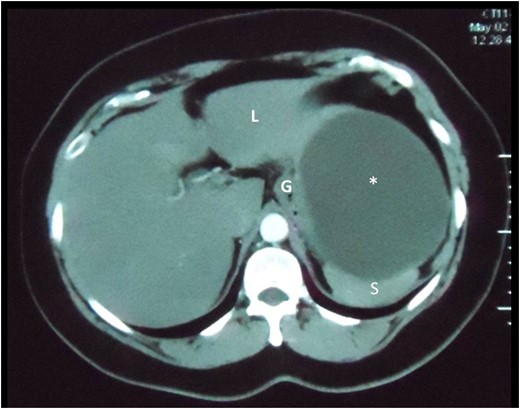

Axial slice of a CT scan demonstrating the cystic lesion that is intimately related to the spleen (S), gastric body (G) and liver (L). A clear plane between the cyst and these organs cannot be demonstrated.

Reconstructed saggital and coronal views of a CT scan of the abdomen demonstrating the hepatic cyst (asterisk) in the sub-diaphragmatic space. The cyst is intimately related to the spleen (S), liver (L) and gastric body (G). The organ of origin cannot be determined from CT scans.

On ultrasonography, they appear as small intra-hepatic lesions with mixed echogenicity [5]. They often appear as target lesions, with central hyper-echogenicity due to cholesterol crystals precipitating out of solution within the dilated BD [6]. On CT scans, VMCs appear irregular with low attenuation areas that do not enhance normally with contrast [5].